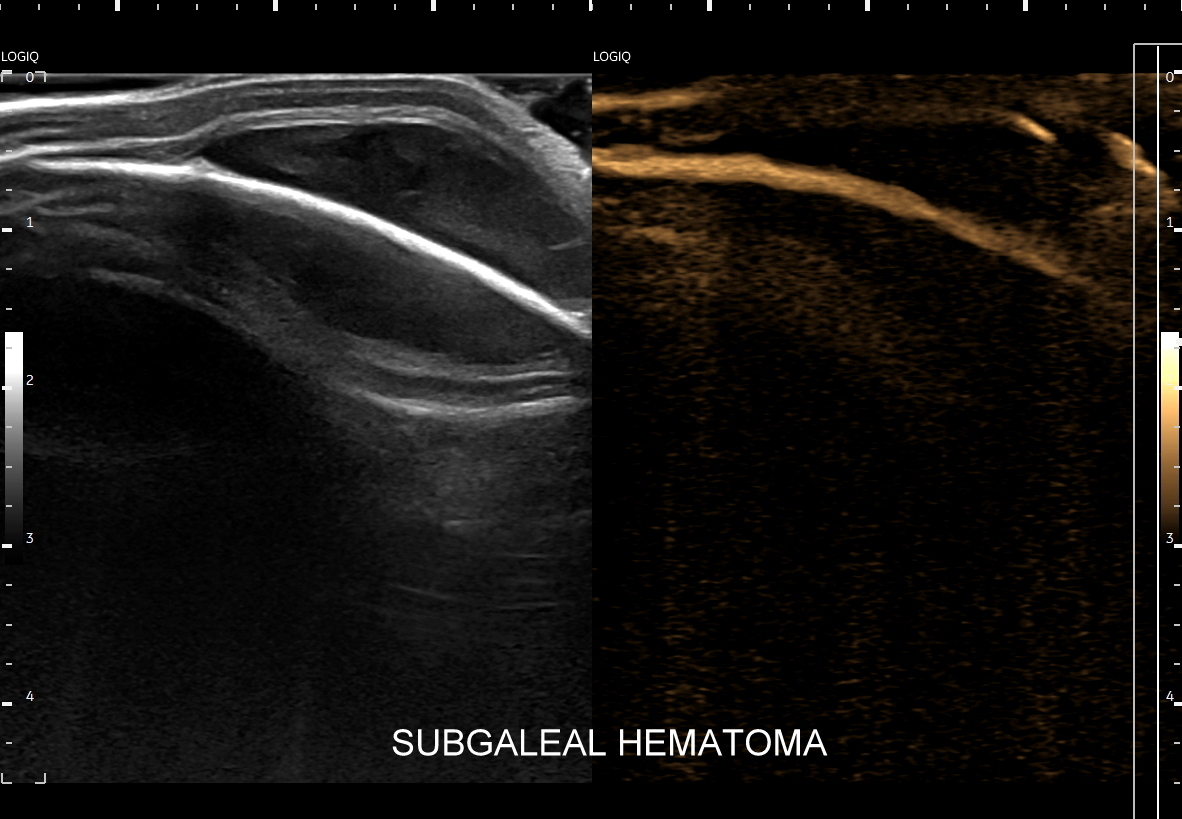

Oprócz zastosowań stricte naczyniowych tryb B-flow znajduje zastosowanie przy poprawie obrazowania struktury narządów wewnętrznych i ich zarysów. Otóż wykorzystując zasady powstawania obrazu w tym trybie, tj. generowanie silnego sygnału, który odpowiada poruszającemu się elementowi, przy implementacji delikatnych acz zdecydowanych ruchów głowicą USG, w ruch można wprawić cały narząd lub grupę sąsiadujących struktur, przez co możliwe staje się stworzenie obrazów struktur miąższowych oraz całych narządów. Jednocześnie stosując odpowiednio intensywny ruch litych struktur tkankowych można niejako oszukać software, tj. oprogramowanie aparatu dokonuje supresji sygnału poruszającej się krwi, przez co uzyskuje się obraz danego narządu o znacznie większej kontrastowości i szczegółowości aniżeli w podstawowym obrazowaniu w skali szarości (w trybie B).